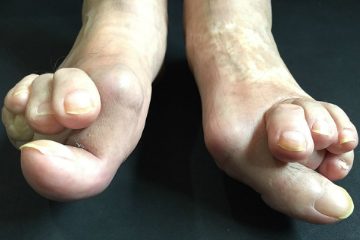

外反母趾は症状、変形、疼痛の痛みの具合は様々です。

外反母趾の問題は疼痛(とうつう)、痛みだけではありません。

・外反母趾での疼痛(とうつう)

・外反母趾の変形症状による身体を支える機能の低下、消失

・ハンマートゥ

・足の関節炎など

これらは外反母趾の方に見る外反母趾以外に抱える悩みや症状などです。